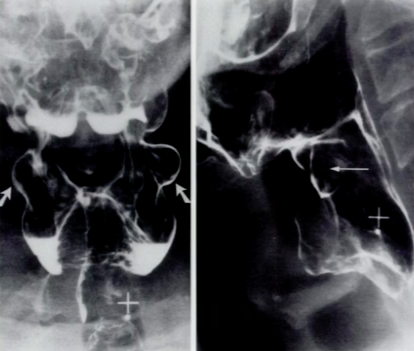

What is your diagnosis?

Lateral pharyngeal pouches from weakening in the mucosa. These can eventually become diverticula and present with halitosis.

There is a mass blocking flow of the barium during the swallow indicating a filling defect. This is a large squamous cell carcinoma.

What could be causing the asymmetry seen on the right side of the image shown below?

It is a slight filling defect, it could be an early carcinoma.